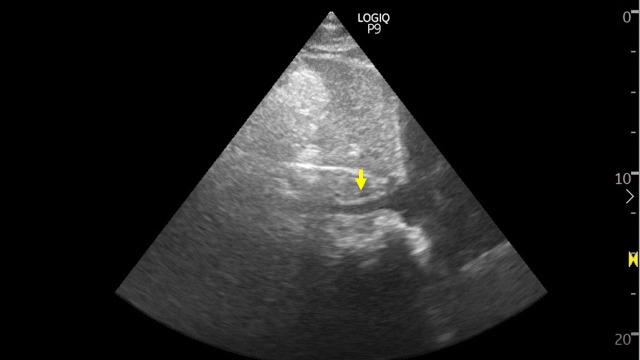

Point of care ultrasonography can be a valuable adjunct to conventional physical examination in patients with hyponatremia that aids in clinical decision making. It can address the shortcomings of traditional volume status assessment such as the inherent low sensitivity of 'classic' signs such as lower extremity edema. Herein, we present a case of a 35-year-old woman where discrepant clinical findings led to confusion in the accurate assessment of volume status but addition of point of care ultrasonography helped to guide the therapy.

对于低钠血症患者,床旁超声检查可作为传统体格检查的重要辅助手段,有助于临床决策。它可以弥补传统容量状态评估的不足,比如像下肢水肿这类“典型”体征固有的低敏感性。在此,我们报告一例35岁女性病例,其临床检查结果存在差异,导致在准确评估容量状态时出现困惑,但床旁超声检查的加入有助于指导治疗。